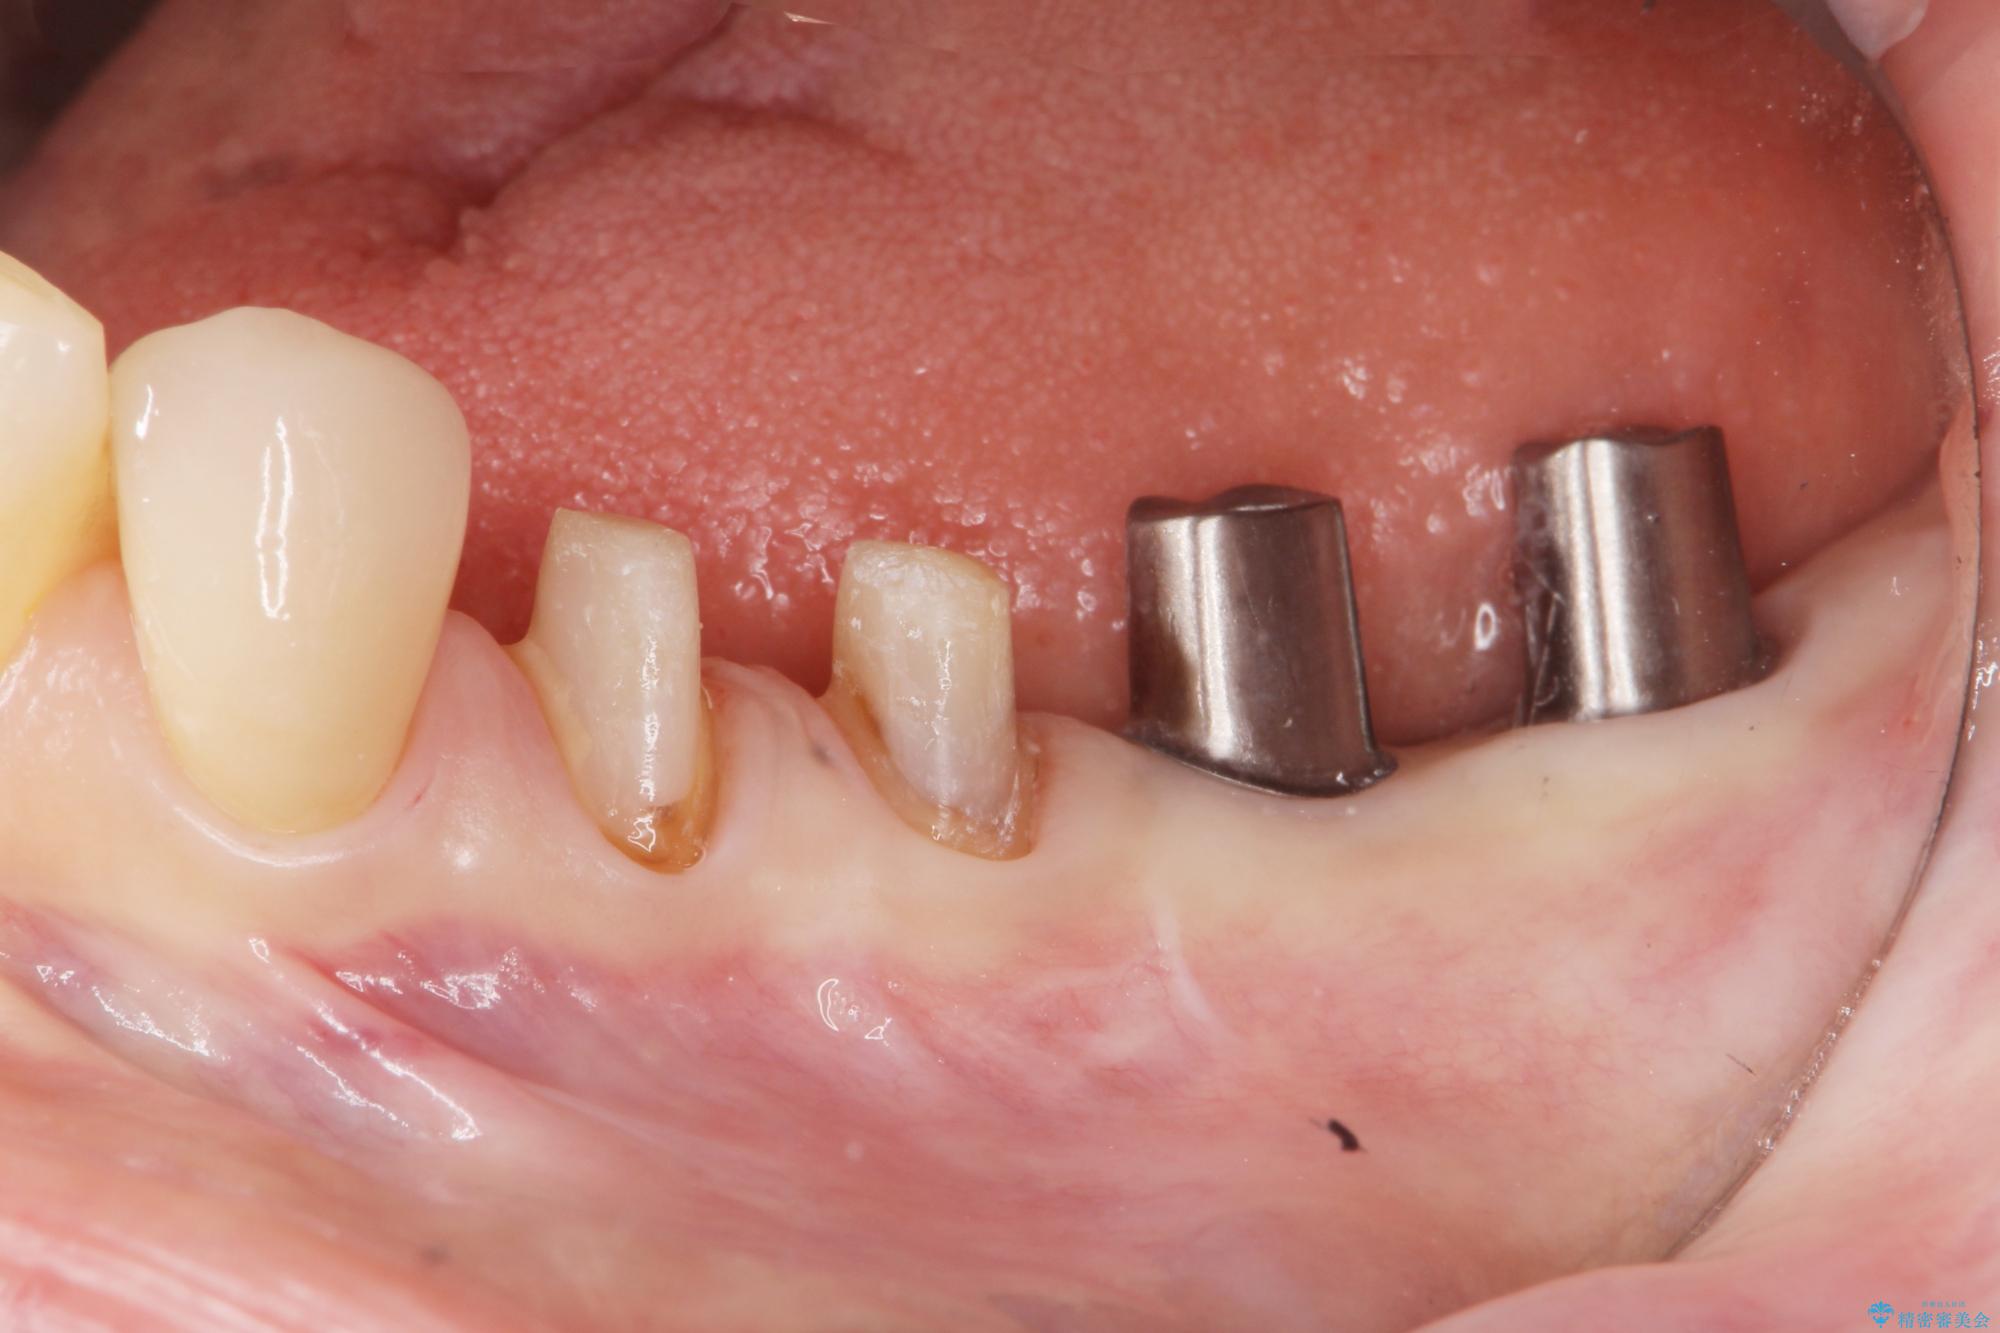

治療前

劣化の進んだブリッジの再治療[ 不適合な補綴物による虫歯の再発 ] 治療前画像 劣化の進んだブリッジの再治療[ 不適合な補綴物による虫歯の再発 ] 治療前画像 劣化の進んだブリッジの再治療[ 不適合な補綴物による虫歯の再発 ] 治療前画像

治療中

劣化の進んだブリッジの再治療[ 不適合な補綴物による虫歯の再発 ] 治療中画像 劣化の進んだブリッジの再治療[ 不適合な補綴物による虫歯の再発 ] 治療中画像 劣化の進んだブリッジの再治療[ 不適合な補綴物による虫歯の再発 ] 治療中画像